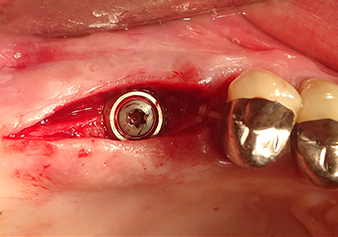

Implantation and prosthetic restoration

To move the augmentation material in the direction of the maxillary sinus atraumatically, the implant was inserted very slowly by hand (Fig. 9). In the process, the membrane was pushed in the cranial direction once again. After two months, the surgical site healed without irritation. Six months later, the x-ray check showed a significant increase in opacity as an indication of ossification (Fig. 10). The prosthetic restoration was carried out with a metal-ceramic crown.